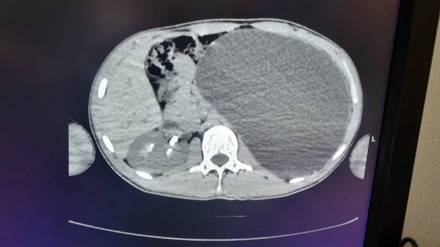

Фото: Минздрав Новосибирской области / Telegram

Новосибирские врачи удалили 17-летнему юноше почку размером с пятилитровую бутылку, которая занимала почти весь объем живота. По словам медиков, такое отклонение было «бомбой замедленного действия». Об этом в среду, 18 февраля, сообщили в пресс-службе регионального Министерства здравоохранения.

— У нашего пациента почка достигла размеров пятилитровой бутылки! Она занимала почти весь объем живота и давила на все соседние органы. Это была настоящая «бомба замедленного действия»: любая травма, случайный удар в живот — и мешок мог разорваться внутри, — сказали в ДГКБ № 1.

В ведомстве рассказали, что хирурги откачали всю скопившуюся жидкость через четыре небольших прокола и удалили орган. Врачи уточнили, что пациент уже идет на поправку, сказано на сайте Минздрава.